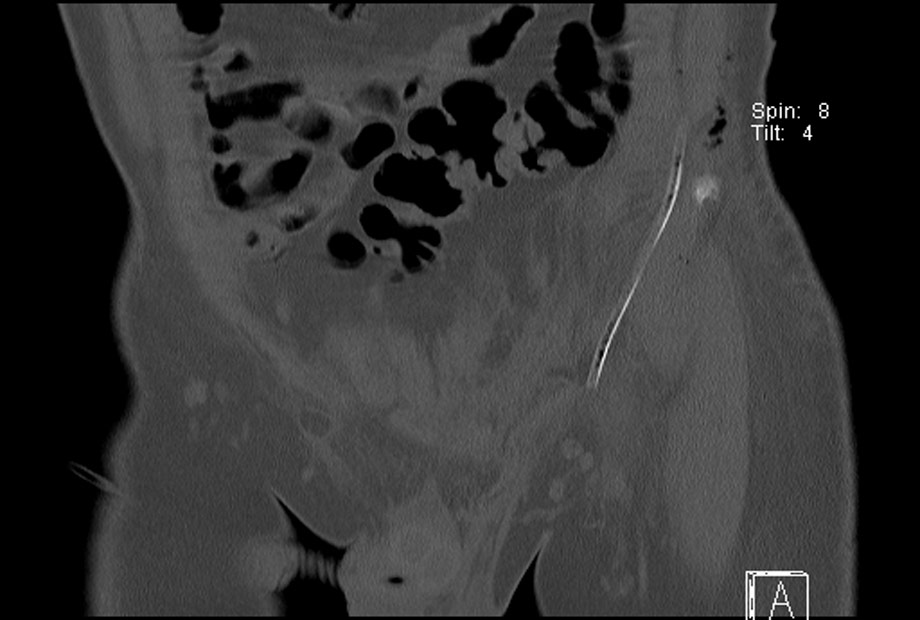

TorenArie Van Geest Ruht Alvarez Marie Louise Elshout No TradeTorenChris Inperspective (Chris Walton)Naomi de RooijDavid Magdalena Loosdrechtseplassen from ZuidzijdeClosed-DoorEighty-EightKuin HeuffSnow-LightLoosdrechtseplassen Let it snow! TorenTorenRaphaël Helle TorenTorenBoxing Dayin my bedroom Torenfrom GoesMarie PopMariken HeijwegenWoosje StuartJulian BarryJet SiemonsTrack of TimeDaan Den Houter TorenThree WindowsZero WindowsMelle de BoerEd van der ElskenMax Genberg HerfstspiegelOutside In Eat more Kalvköttbullar with whiskeygräddsåsfrom Malmöthe World DaphneWorld Famous BurgersFour WindowsClosed-DoorEat more Smørrebrødsays: The Little MermaidClosed-Doorfrom KøbenhavnStructure-collagesMorning Mist-LightTorenTorenWhite stripe-LightTorenTorenTorenLeo de BieShizen Naeh Tsie-Chun-SioeTorenAd van de DonkTheo HuijgensGlobal warming!!!!!Het Oude PosthuisRene MagritteStructure-collagesLoosdrechtseplassen TorenAnnemarie Slobbe-Light Benoit DestenayBenoit DestenayBenoit DestenayClosed-DoorVan GoghBenoit DestenayClosed-DoorStructure-collagesBenoit DestenayFenix museum Every Two WeeksClosed-DoorAlexander GroenewegeAnnemarie SlobbeMohand AbttoyJuan Heinsohn HualaLilia GarridoMichael BomCentraal Museum UtrechtLoosdrechtseplassen TorenBirgitta Sundström JansdotterLoosdrechtseplassen Loosdrechtseplassen Closed-DoorNelis OosterwijkAstrid van RijnTorenWilma Kun BrandenburgShanDavalosLoosdrechtseplassen Full Moon LightGlobal warming!!!!!Mothers Dayfrom Emmerich am RheinTorenLoosdrechtseplassen DublinClosed-Door Eat more BoxtyDublinDublinfrom DublinMonument of LightLoosdrechtseplassen Gate to DeathLoosdrechtseplassen Annelies de GreefParisa AkbarzadehAstrid van RijnLoosdrechtseplassen Magda MendesClosed-DoorLoosdrechtseplassen Thé Van Bergen Casper PragerLoosdrechtseplassen Torenfrom Tilburga TreeClosed-DoorClosed-DoorLoosdrechtseplassen BagGebouw de MaasClosed-DoorLoosdrechtseplassen Cleaning Ladyand her driver! Louise du ToitChristine Impey Loosdrechtseplassen Carine HooykaasFrank van Polanen PetelTamara JungnickelIngrid SlaaLeidenLoosdrechtseplassen Closed-Dooren meer!Loosdrechtseplassen Lauran van Oers...this gate is not goldenBirthday-GirlLoosdrechtseplassen Thrift storeLoosdrechtseplassen Lucie BoucherotRaphael HelleTorenTorenTorenThe Breath of Ohara KosonIt’s a golden girl !Boxing DayChrist-mist-LightSluisGlobal warming!!!!!M.T.A.Boschfrom BrugesLoosdrechtseplassen Loosdrechtseplassen TorenLoosdrechtseplassen Loosdrechtseplassen Loosdrechtseplassen Atie KeizerwaardVlaardingenLoosdrechtseplassen Torenfrom Dongenfrom Udenfrom GeldropTorenTorenGlobal warming!!!!!Closed-DoorJohannes SteendamVince BlokEye InfectionLoosdrechtseplassen Gabriella Davalos ArayHans Peter WesselsSander BuijkRon van der EndeHugo LammerinkLoosdrechtseplassen TorenLoosdrechtseplassen Antoine UitdehaagOndine de KroonLiesbeth van MoorselHamid El KanbouhiAbdelkader BenaliTorenLoosdrechtseplassen Final PortraitMorphine TreatmentLast breathLoosdrechtseplassen Ham sandwichRotterdamLoosdrechtseplassen Loosdrechtseplassen from AlkmaarIdentity cardfrom ZevenaarLoosdrechtseplassen Loosdrechtseplassen Storm-Rain-Lightthe skyXTorenLoosdrechtseplassen Loosdrechtseplassen Frits Anton van der Horst (Pijnacker, 1946 - Still Alive)Ninety-two yearsLoosdrechtseplassen TorenLoosdrechtseplassen from BergambachtPoppyEgberdien van RossumYvonne van der HavenMothers DayTelescoop glassesLoosdrechtseplassen CystitisTorenLoosdrechtseplassen Rain-LightTorenFernanda Dos ReisTorenLoosdrechtseplassen Irem Kaneli and Stijn SmitM.T.A.Boschfrom Berlikumfrom LeeuwardenLoosdrechtseplassen Remembrance of the Dead / Liberation DayTorenTorenLoosdrechtseplassen King William of Orange-LightTorenGrey Day-LightLoosdrechtseplassen Daphne BomBarbara Palandeng-MunselKarin de Visser Ruth Horstmanshoff Bima Engels Loosdrechtseplassen TorenHail Storm Rainbow-LightKinan AzmehJeroen van Vliet and Kinan AzmehAfternoon napLoosdrechtseplassen TorenGEB buildingWilliam Barrett – bass Loosdrechtseplassen Loosdrechtseplassen Loosdrechtseplassen SpringNiloe HedayatLoosdrechtseplassen Loosdrechtseplassen Closed-DoorLoosdrechtseplassen Loosdrechtseplassen Loosdrechtseplassen Yellow Morning LightBirthday-GirlLoosdrechtseplassen Closed-DoorLoosdrechtseplassen Boxing DayLilac Lightthe skyLoosdrechtseplassen Loosdrechtseplassen from Bussumfrom HilversumLoosdrechtseplassen from Noordwijkerhoutwhen the bomb explodes?from Arkelfrom DoornLoosdrechtseplassen from DriehuisSuch parents, such children! Pink Marieke LightLoosdrechtseplassen from RenswoudeLoosdrechtseplassen Loosdrechtseplassen Carine Hooykaas Marjoke SchultenAnton Vredefrom Waalwijkfrom Lieropfrom HelmondRoman Catholic church St. John the Baptistfrom Liège from AachenKai Ouden MeneiThe BirdsThe camera is still rollingAachener DomAerial work platform WorkersJeroen Allartat the North Seafrom ZutphenHouseLoosdrechtseplassen PheasantLoosdrechtseplassen SunglassesLoosdrechtseplassen Global warming!!!!!Loosdrechtseplassen Loosdrechtseplassen Gyz La RivièreClosed-DoorLoosdrechtseplassen Loosdrechtseplassen The Woman and the DoveClosed-Doorfrom Alphen aan den RijnTorenLoosdrechtseplassen Torenabove ErasmusCreedence Clearwater RevivalLoosdrechtseplassen Eric StofmeelOPENJanneke.StofmeelPaul Vinkenthe skyfrom DelftLoosdrechtseplassen CloudLoosdrechtseplassen ZevenaarFather's DayLoosdrechtseplassen Loosdrechtseplassen Andra DaansDickie LeatemiaRobin Nortee Loosdrechtseplassen Wilma Kun Nintey-one years Mothers DayCharlie KoolhaasWelcome to the ClubNothing Natural Meaof Springabove ErasmusRainbow Nation LightLoosdrechtseplassen Ruud GoedhartLoosdrechtseplassen Jurriaan MolenaarJeroen Allartfrom ‘s-Hertogenbosch above ErasmusLoosdrechtseplassen Loosdrechtseplassen SpringRetirement ageLoosdrechtseplassen from OostvoorneBracesLoosdrechtseplassen Rose leaves pink LightIda Vierwind (85) and Marietje Vierwind (86)Jeroen AllartJennifer Smith DaphneLoosdrechtseplassen Cruising Junction Raasdorp inAlexander GroenwegePrincess Pink-LightLoosdrechtseplassen Loosdrechtseplassen Loosdrechtseplassen Grey New Year- LightBird's Shadow ChristmasLoosdrechtseplassen Orangemorning-LightLoosdrechtseplassen RaboTowerLoosdrechtseplassen Structure-collagesToren from MaarssenRotterdamShell buildingNobodyNobodyClosed-DoorAndré van der VeekeKoningshavenbrugLoosdrechtseplassen from KleveDaphne BomOld Ladies Pink-LightLoosdrechtseplassen over waterEndsMaher Al SabbaghStairway to SunriseTorenTorenLoosdrechtseplassen TorenMichael BomLucy Havel RotterdamPink Storm-Lightabove ErasmusMarieke Abelman Pink-LightLoosdrechtseplassen of YouthClosed-DoorGebouw Delftse PoortGlobal warming!!!!!from OstendVenetian GalleriesMeaStructure-collagesClosed-DoorCovid-19Heat Wave LightLoosdrechtseplassen Father's DayLoosdrechtseplassen Jeroen Sloof Loosdrechtseplassen New LifeDead in StrasbourgBenoit DestenayStructure-collagesMouthfrom Maastrichtfrom BeverwijkCataract Surgerythe skyNinety yearswith her Susan Bijl BagMothers DayClosed-DoorThea de Bruin & Jan de BruinRotterdamSeñora Huertafrom Heilig Landstichtingfrom AlmereTorenfrom MiddelburgFrank HanswijkJannes Lindersfrom UtrechtCape TownMarcel Theodore Anthony Bosch Joe Sterck from s-Gravelandfrom LeidenLoosdrechtseplassen Loosdrechtseplassen from HaarlemCemetery St. Petrus Bandenfrom Den HaagRobert Schuurmans StekhovenDaphne BomCologne CathedralClosed-DoorCologneand the door down to Hell?Vollstaendiges Endefrom CologneThe Russo-Ukrainian WarEltenbergWijde BlikDaan den HouterZutphenN204, 177, 80Aji Valliathu Narayanan Orange-LightGolden Morning LightHappy New Year LightMorning Sun-LightOrange Cloud Color LightColor Purple LightRalf KokkeStructure-collagesDick RonteltapTorenTorenTorenVolkswagenGlobal warming!!!!!Found a woman in the woods!M.T.A.BoschM.T.A.BoschM.T.A.BoschFlak bedding ParkOllie Quist9-11 LightClaes de VrieselaanClosed-DoorClosed-DoorHoge Veluwe National ParkGermaine Sandersfrom ZoeterwoudeJan de BruinM.T.A.Boschthe skyEline StrijkersNola Minolfi ELfie KristianaMarijn van ZessenMarijn van ZessenMadelon VerbeekGrey Rain Clouds LightKralingse BosBrian JanssenRotterdam-OrangeGlass house-worldPeacedoes not smoke because of love!Day of the Workers LightHis first mustache!Global warming!!!!! brings a mysteryGray Goose The environment of man is his fellow man!!!Corner Cloud CompositionSchiedamdoes not smoke because of love!does not smoke because of love!Corner Cloud CompositionAndre Smits.does not smoke because of love!Glass house-worldWinter Snow-Storm LightJanis JoplinCorner Cloud CompositionCorner Cloud CompositionWinter-Snow LightCorner Cloud CompositionCorner Cloud CompositionBlue White Grey Winter-LightOrange light in the evening The environment of man is his fellow man!!!Pink light evening skyDawn-stripe of light The environment of man is his fellow man!!!CloudDead Shark in my neighborhooddoes not smoke because of love!Corner Cloud Compositiondoes not smoke because of love!does not smoke because of love! Grey Clouds SymphonyCorner Cloud Compositiondoes not smoke because of love!Corner Cloud CompositionAji Valliathu Narayanan White Cloud Storm LightWhite Blue Storm Lightdoes not smoke because of love!BlackCorner Cloud Compositionat the North Seadoes not smoke because of love! The environment of man is his fellow man!!!does not smoke because of love!Corner Cloud Compositiondoes not smoke because of love! The environment of man is his fellow man!!!does not smoke because of love!Le quattro stagionidoes not smoke because of love! The environment of man is his fellow man!!!does not smoke because of love!Corner Cloud Composition The environment of man is his fellow man!!!does not smoke because of love!Bird's Shadow du soleilCorner Cloud CompositionMagicalOrange Storm Evening Summer-Light The environment of man is his fellow man!!! The environment of man is his fellow man!!! The environment of man is his fellow man!!! The environment of man is his fellow man!!! The environment of man is his fellow man!!!Corner Cloud CompositionJeroen AllartJeroen AllartOrange Storm Summer-LightCorner Cloud CompositionCorona SunsetsCorona SunsetsCorona SunsetsCorona SunsetsCorona SunsetsCorona SunsetsCorona SunsetsCorona SunsetsCorona SunsetsCorona SunsetsCorona Sunsets The environment of man is his fellow man!!!Corona Sunsets The environment of man is his fellow man!!!Corona SunsetsCorona SunsetsCorona SunsetsCorona SunsetsCorona SunsetsCorona SunsetsCorona SunsetsUnderwater LightCorona SunsetsCape TownCorona SunsetsCorona Sunsetsabove ErasmusCorona SunsetsFatmaCorona Sunsetsabove ErasmusCorona Sunsetsabove ErasmusCorona SunsetsCorona SunsetsCorona SunsetsCorona SunsetsCorner Cloud CompositionCorner Cloud CompositionCorona SunsetsCorona SunsetsCorona SunsetsCorona SunsetsCorona SunsetsCorona SunsetsCorona SunsetsCorona SunsetsCorona SunsetsCorona SunsetsCorona SunsetsCorona SunsetsCharlie KoolhaasGnome predictionsCorona SunsetsDiana Basyouni Al-HalabiLove StoryCorona SunsetsDiana Basyouni Al-HalabiCorona SunsetsCorona SunsetsCorona SunsetsCorona SunsetsCorona SunsetsCorona SunsetsCorona SunsetsThunder Lightthe skyCorona SunsetsCorona SunsetsCorona SunsetsCorona SunsetsCorona SunsetsCorona SunsetsCorona SunsetsTransylvanian LightCorona SunsetsFull Pink Cloud Moon Lightabove ErasmusCorona SunsetsCorona SunsetsCorona SunsetsCorona SunsetsCorona SunsetsCorona SunsetsCorona Sunsets The environment of man is his fellow man!!!Corona SunsetsCorona SunsetsCorona SunsetsCorona SunsetsCorona SunsetsCorona SunsetsCorona Sunsetsis FloodingCorner Cloud CompositionCorner Cloud CompositionCorona SunsetsCorner Cloud CompositionCorona SunsetsCorona SunsetsCorona SunsetsCorona SunsetsCorona SunsetsCorner Cloud CompositionCorner Cloud CompositionCorona SunsetsCorona Sunsets The environment of man is his fellow man!!!Corona SunsetsCorona SunsetsCorona SunsetsCorona SunsetsCorona Sunsets The environment of man is his fellow man!!!Corona SunsetsCorona SunsetsCorona SunsetsCorona SunsetsCorona SunsetsCorona SunsetsCorona SunsetsCorona SunsetsCorona SunsetsCorona SunsetsCorona SunsetsCorona SunsetsGrey Morning Spring-LightGlass house-worldFlamingo-Pink LightCorona SunsetsUnknownCorner Cloud CompositionCorona Sunsetsen DauwCorner Cloud CompositionBird's Shadow Bird's Shadow does not smoke because of love! The environment of man is his fellow man!!!Bird's Shadow Bird's Shadow Corona Sunsets The environment of man is his fellow man!!! The environment of man is his fellow man!!! The environment of man is his fellow man!!!When the night has come. The environment of man is his fellow man!!!Nose CandyPurple Haze-Light The environment of man is his fellow man!!!UnknownLove LettersUnknownRene DuinkerkenCharlotteCorner Cloud CompositionOrange-Light The environment of man is his fellow man!!! The environment of man is his fellow man!!!does not smoke because of love!Corner Cloud Compositionof the dayUnknown Unknownhas left the Buildingof the dayCorner Cloud CompositionNew Years Firework-LightUnknownBird's Shadow Kai Ouden MeneiOrange Morning-Light The environment of man is his fellow man!!!DaphneCorner Cloud CompositionMurkiness LightIbrahim MaaloufHeba MalaebCorner Cloud CompositionJimdus Aka Jimmy Onrustat the North SeaMastrubation Mastrubation White Cloud Storm LightRotterdamUnknownUnknownUnknownUnknownCorner Cloud CompositionCorner Cloud CompositionCorner Cloud Compositionen DauwCorner Cloud CompositionUnknownUnknown.........WaitingCorner Cloud CompositionUnknownUnknownPlanet Claire Air Lightthe skyUnknownPowder box LightMoon LightGlass house-worldUnknownUnknownYuichi HirakoGrey Rainy Cloud LightUnknownUnknownUnknownUnknown has Pink Airhas gold in its mouth Glass house-world has Pink AirCorner Cloud Composition Cities of GlassUnknownUnknownUnknownUnknownUnknownCorner Cloud Composition Corner Cloud Composition Grey White Cloud Light UnknownUnknownPara KrizhnaCorner Cloud Composition Corner Cloud Composition Corner Cloud Composition Corner Cloud Composition Dark Evening Light Corner Cloud Composition Corner Cloud Composition Rostov-on-DonUnknownPhoenixUnknownUnknownUnknownUnknownIce crystalsCorner Cloud Composition permission to land!Blue Light Cloudy Evening Light Unknownis my holy passionRed Light ( District.)the skyUnknownUnknownUnknownUnknownUnknownUnknownUnknownUnknownUnknownNederlands FotomuseumCorner Cloud Composition is altijd groenerit already endsit already endsRotterdamDelfse PoortLaurent Med Khellout Corner Cloud Composition Corner Cloud Composition Stormy Rainy Light UnknownBram PeperUnknownfrom MuscatHyderabadfrom Hyderabad Divya GulechhaDaphne BomEat more Biryani.Be sure to wear some flower in your hair!Be sure to wear some flower in your hair!matching Clothing!Green HyderabadNightsBalrajGulechhaDivya GulechhaMaría Jose Palacios MariaUnknownCorner Cloud Composition Strawberry and Cookies & CreamStormy Evening Light Glass house-worldEvening Sunset Light Stormy Day lightabove ErasmusRotterdamCorner Cloud Composition UnknownUnknownCorner Cloud Composition Corner Cloud Composition UnknownWilma KunAnique WeveRobin KollemanCorner Cloud Composition Edith Meijering DaphneCorner Cloud Composition Corner Cloud Composition Winter LightCorner Cloud Composition Schiedam het theater verlaten heeft............Corner Cloud Composition the skySelfie with VloeimansCorner Cloud Composition Corner Cloud Composition Orange lineCorner Cloud Composition SchiedamMorning Dawn LightCorner Cloud Composition Corner Cloud Composition Lasiocampa quersusCorner Cloud Composition Corner Cloud Composition St. Joris Bierfrom Den HelderTexels Speciaal BierM.T.A.Boschfrom Oudenboschfrom RaamsdonkWhen the Soul leaves the buildingCarotid Artery SurgeryFluorescent DawnMusculusDe Prael Bierfrom AmsterdamDe 7 Deugden BierDe Koperen Kat BierEvening-Light on a Cloudy Day Corner Cloud Composition Corner Cloud Composition Sunset LightCorner Cloud Composition Hiroki MatsuuraNoordwijker StrandDrawingCorner Cloud Composition Momoof a Black BirdWave CloudsCorner Cloud Composition Blood MoonPigeonPterophorus pentadactylarolls a JointRachel WuSelfportrait Golden HourCorner Cloud Composition Avishai CohenAvishai CohenCorner Cloud Composition THOMS BierCorner Cloud Composition Corner Cloud Composition Sun-Light on a Cloudless Day Jeroen Allart Light Corner Cloud Composition Full Moon by Night LightCorner Cloud Composition Full Moon by Evening LightCorner Cloud Composition ZevenaarCorner Cloud Composition BosCorner Cloud Composition CloudySunsetCorner Cloud Composition Corner Cloud Composition Le quattro stagioniDat ik u kusHazy Before SunsetUnknown girlCorner Cloud Composition After SunsetCorner Cloud Composition Corner Cloud Composition Corner Cloud Composition Mire!!!!Kaapse Brouwers BierCorner Cloud Composition Glass house-worldCorner Cloud Composition Corner Cloud Composition Corner Cloud Composition OvercastNoordt BierCorner Cloud Composition Corner Cloud Composition Jonkheer BierCorner Cloud Composition 07:20Cities of GlassCities of GlassGlass house-worldCorner Cloud Composition Corner Cloud Composition Babberichis BurningGlass house-worldPink HourGlass house-worldCities of GlassLandLandLandGlass house-world07:30Corner Cloud Composition Glass house-worldAdolfo Estrada VargasCorner Cloud Composition Corner Cloud Composition Corner Cloud Composition Corner Cloud Composition Corner Cloud Composition Corner Cloud Composition Corner Cloud Composition Corner Cloud Composition Corner Cloud Composition Corner Cloud Composition Corner Cloud Composition Corner Cloud Composition Dawn XMorning LightgrondsopgrondsopCorner Cloud Composition Le quattro stagioniCorner Cloud Composition Josef KaJosef KaCorner Cloud Composition Corner Cloud Composition Corner Cloud Composition Corner Cloud Composition Corner Cloud Composition Corner Cloud Composition Corner Cloud Composition Corner Cloud Composition Corner Cloud Composition Corner Cloud Composition Corner Cloud Composition Corner Cloud Composition Corner Cloud Composition Corner Cloud Composition Corner Cloud Composition Corner Cloud Composition Glass house-worldCorner Cloud Composition Corner Cloud Composition Corner Cloud Composition Corner Cloud Composition Corner Cloud Composition Corner Cloud Composition Glass house-worldGlass house-worldCorner Cloud Composition Glass house-worldCorner Cloud Composition Unknown Manen DauwGlass house-worldCorner Cloud Composition Half Moon LightCorner Cloud Composition Corner Cloud Composition Corner Cloud Composition Corner Cloud Composition Corner Cloud Composition OoievaarsteegSchiedamTrilogy.........Waitingfrom Piraeusδεν το μυρίζεις;from AthensEvzonenof Athensof Athensof Athensof Athensof Athensof AthensEat more CalamarisEkklisia Isodia Theotokouof Aeginaof AeginaAthenswith her Chanel BagGlass house-worldBlue Dayen DauwGlass house-worldGlass house-worldGlass house-worldNubesEvening LightCorner Cloud Composition RainbowGlass house-worldGlass house-worldhas gold in its mouth RotterdamNight LightRainBlue Hour Day LightCorner Cloud Composition Corner Cloud Composition Where did you been last night !Pasquale Talerico Roots Reggae and Dub-Master Roots Reggae and Dub-MasterRon SteinerRon Hommage Frida KahloJefferson AirplaneCorner Cloud Composition Maurits de BruijnLeon de BruijnLeon de BruijnGraaf van NassauLe quattro stagioni the Sea of FogCorner Cloud Composition Corner Cloud Composition Corner Cloud Composition Fatma & Kamroennisa Corner Cloud Composition Corner Cloud Composition Corner Cloud Composition in the Sky SchermlaanSchermlaanthe skyUnknownDorothy Corner Cloud Composition Maastunnelfrom Scheveningenthe skythe skyLichtCorner Cloud Composition Corner Cloud Composition Corner Cloud Composition Corner Cloud Composition Elizabeth GonzalezEndsDonut knotEndsI can see all obstacles in my way!Pelgrim BierCorner Cloud Composition Corner Cloud Composition Isabel ReitemeyerJohannes Schele Levon PartzschPrater BierTrilogyKarl Marx and Friedrich Engels Ernst-Thalmann ParkBerlinfrom BerlinBerlinPanoramastrasse 1AAlexanderplatzPotsdamer Platz Rosa-Luxemburg-PlatzHouse of RosaStructure-collagesfrom ArnhemCorner Cloud Composition Corner Cloud Composition Corner Cloud Composition Corner Cloud CompositionCorner Cloud CompositionRotterdamCorner Cloud Composition Corner Cloud CompositionN.A. from....N from JapanAffiche in the 1e MiddellandstraatPieter HugoFogNiels Smits van BurgstCorner Cloud CompositionAndre Smits.Corner Cloud CompositionCorner Cloud CompositionLe quattro stagioniof a Black BirdCorner Cloud CompositionSensoryCorner Cloud CompositionGilbert van Drunen, P.MtodayLe quattro stagionien DauwGreat titCities of Glasson the TrainEvergeenMaasvlakte 2 Bleu Rito Ramon ArocheRito Ramon ArocheCheat the beginningLenin ParkFrank Garcia-HernandezViva Cuba LibreJulio Antonio Mella, Camilo Cienfuegos & Che Guevarathe Mafia BarEscuadron de EliteThat the true Revolutionary is guided by a deep sense of Love.Social ClubHavanaBocaditosfor a FriendDairan Fernandez de la FuenteEat more Bistec de Polloenter the Museum of the Revolution.Rolando FernadezArt DecoEl Floriditain El Floriditain El Floriditain El FloriditaMuseo de la RevolucionComision de Defensa de la RevolucionNo Mire!!!!DriveUnion de Jovenes ComunistasMurmulloMurmulloHavanafrom Havanaof Habana Habana Viejaof Habana Fela [Felicia Moracen Naranjo]Air Acondicionado RestauranteNightsHamburguesa y QuesoChicos,Pizza's y LimonadaEduardo Johnson LorettAir Acondicionado RestauranteHavanaof Habana Mojito, Por favor!House of Chea Model for the WorldNo Fumar Exigir lo imposible!Sentado en la entradaPlaza Vieja CervezaBlue HavanaCigarJose MartiErnesto Che GuevaraCamilo Cienfuegos72,000 square meters.Schermlaanen DauwUnknownPien van der BeekPien van der BeekHuma Birgulof a Black BirdJan PorcellisstraatUnknown Bird's Shadow 1:2 3 by night Kroesat the BeachOlafur EliassonNotion motionFranz von Chossy UnknownWeedy AndaWeedy AndaRonnie RotebRonnie & SunnyHarmony of the SeasM.S. Koningsdam................?Le quattro stagioniMeeuwMonika DahlbergRanda ElberyLe quattro stagioniJacco van Giessen en M.T.A.Bosch Yokocola Cellarsounds Studionaar De AkkersFrits Anton van der Horst (Pijnacker, 1946 - Still Alive)Lauran van OersВесна священнаяLe quattro stagioni The environment of man is his fellow man!!!A.M.Unknown girl The environment of man is his fellow man!!!Mosab Anzo Jan Maarten Leupen Jan Maarten LeupenStef van Breugela Pink CloudTime Wagamamafor the Road !Williams Williams Hello...EggLe quattro stagioniBuilding on the TrainA from ItalyAngel MartinezNovember Sun Lichtcomes in a plastic Bag, Amen!Maria KassabDoorDoorPink BeirutMouthfrom BaalbekOffof the Phoenician cityRoman temple complexWhy is it good for! in the past in the past in the pastmeets 21th CenturyDreamsof a David Carradine ExitEntranceHe will judge you!of TripoliVulva !on the WallCentreon the WallFather Ibrahim Sarrouj s Bookshopway LightStructure-collagesAntoine Haddad, Owner-operator at Artlab between East and West BeirutKijkenPoolin the Cloudsin the CloudsVincent Mentzelis de mede MensJulius Anton (Jules) Deelderfor the Road !Global warming!!!!!Ahmet Yunus OğlüKissUnknownNieuwe Binnenweg Le quattro stagioniEndsP.M.the skyat the Ryan McGinley exhibitionPhalera bucephalaArmandArmandТеодора ЦвикинаТеодора ЦвикинаТеодора ЦвикинаCharlotteLichtLichtLichtLa Reproduction interdite (Not to be Reproduced)MSC Orchestrain the Morningfrom Luxembourg-CityMorning-GloryThe Kitchen The Kitchen The Kitchen The Kitchen Eat more Fierkelsjhelli Krystel Antoni Skaf S'il vous plait me donner un peu d'argent!Laurence Longueville, Visual ArtistEat more Schwarzwalder Schinken Nicolas Serge Zimny Renee Everaert A Tinder Operafrom Dordrechton our way to Emmerich am Rheinon our way to Emmerich am Rheinon our way to Emmerich am RheinRotterdamBagEat more Croque Ciriopour la Mort Subitedans Brasserie-Taverne GreenwichMaaloufMaaloufNRC NextEat more Wiener SchnitzelCafe EilesWurstwaren ErfrischungsgetrankeHofburgUnknownPeterskircheDie Presse from Viennaa Pink CloudBilal Giuseppe LicariGiuseppe LicariGreen Green Grass Of Home slipped under white,cold lightning.Ana Breton AguilarOriginal SinLaamariSubway Station Maashaven Museumon the Swingon the Swingon the SwingStormSvetlana PrigoditchSvetlana PrigoditchSvetlana PrigoditchSvetlana PrigoditchSvetlana PrigoditchSvetlana PrigoditchWitte de WithstraatRotterdamMashrou LeilaSelfie het theater verlaten heeft............Gerrit Jan Mulderstraat 2-AHeemraadsingelwas here!SS Rotterdam and think of somewhereuntitled 14Igor Stadoljev Igor Stadoljev Igor Stadoljev Igorstreet surrealismLunch BoxMusculus MeaMeaCentral StationDinnersStadsparkvan Antwerpenonly MyselfUnder Construction Pink TreeClosed-DoorRotterdamStationonly MyselfDen HaagSean Christopheruntitled 19Eat more Pie & Mashfrom LondonUnknownUnknownNelson MandelaUnknownPrimrose GardensRaboTowerBlaakmetrostationKrystel Skaff AntoniBep de BruinDe RotterdamDe RotterdamDe RotterdamDe RotterdamRotterdamDaphne Maria BomLaurenskerkde Stoombootin the WallRoue de BicycletteSchermlaanRotterdamCreedence Clearwater RevivalDo!Die ErsteDer Letzteof the Berlin WallExistenceBerlinBerlinBerlinEast Side GalleryEast Side GalleryEast Side GalleryBerlinBerlinBerlinBrunnen StrasseBerlinBerlinBerlin1963BackBackBackChairBrandenburger TorHamburger Bahnhof Museumuntitled 18ShellgebouwGebouw Delftse Poortvan Xiavan XiaKonijnen afRotterdamToiletSchermlaanPernisZevenaarThe Prime TowerZurichEat more GeschnetzeltesHistory!LandedFrom A. to Z. DaphneZurichfrom Zurichthe New KingWhere does the world come from?Grand Palaisin Rotterdam, its in the bag?saunter at Mariendaal inSaki MatsuuraMatsuuraMatsuuraMatsuurade Barbier van Rotterdamde Barbier van Rotterdama Distance;Downtown Witness!Downtown Witness!The EggComeBeirutdoes not grow Hair!Omaya MalaebHassan Abo Schermlaan-WhiteCuriewegSchermlaanSchermlaanQueen Mary 2Schiffermutzecasi sulla StradaLambEric Pfisterfrom StrasbourgEye don't Love youfrom BorkumUnknownBorkumBorkumAstronautMother EarthBorkumPoolEat more TapasUnknownActress: Omaya MalaebMoritz Cervezavan der Rohe van der Rohe from BarcelonaWattwegPeoplePhil BloomHaig PapazianAji Valliathu NarayananAji Convivial SoulM. T. A. BoschM. T. A. BoschM. T. A. BoschMaher Al SabbaghM. T. A. BoschEgberdien van RossumMarcel T. A. BoschM. T. A. BoschM. T. A. BoschM. T. A. BoschM. T. A. BoschM. T. A. BoschM. T. A. BoschM. T. A. BoschM. T. A. Bosch Souls SoulsHenk DirkerJason Ross LawsonLombardkadeM.S. RotterdamOneuntitled 17from AmmanOmaya and Anoudon the EarthEat more Mansaf matching Clothing!LizardArab SpringPeopleRockRockUnknown700 Steps to Robinson's High PlaceThe TreasuryPoolPetraPetraPetraUnknown manof the Um Tomb1200 meters long1200 meters longGuardGuardFacadeFacadeStadStadSea of SaltSea of SaltSea of SaltUmayyad bath-houses Blocks................... Raafat MajzoubRaafat MajzoubUmayyad Mosque Citadel.SpringRotterdamfrom RotterdamTomtitRotterdamRotterdamSexual DependencyNan GoldinNan GoldinNan GoldinJoost Zwagerman (Alkmaar, 18 november 1963 - Haarlem, 8 september 2015)RotterdamMaria's OrgasmQueen MariaMinder MariaThe PopeBianeo CosimoEat more Carciofoin the streets of RomeRomeout the NecropolisBasilica Museo VaticanoBasilica Chiesa NuovaBasilica Saint PetersPantheon GamesRomaVatican CityVatican CityRomaKai Ouden Meneiof AdamGod is goneout of Heavenfrom Romefrom Vatican Cityagainst oneUnknownEmscherlollieuntitled 15untitled 16Agnieszka WojciechowiczSelfportrait Agnieszka Selfportrait Tineke and DaphneLouise and Jeroenuntitled 22Harlot Mariathe Ant EaterI met in BeirutYou bleri poepholDaphne Bom, the Submarine WharfGeminate SoulJ from CanadaJune, 2010on Starboard SideParisParisParisParisEat more EscargotsM. T. A. BoschParisParisIcarusUnknown girlLucie BoucherotFeast of the flies!from ParisPariswith Love Andrew TangCaro BaumannEbb and FloodEat more Boerenkool met WorstMelle de BoerMelle de BoerBeaMartinDowntown Witness!Downtown Witness!OOOOO = hotelThe ClientEat more SakaakirMastic Ice Cream with PistachiosIce CreamIce CreamIce CreamDead in Hamra(t)GoUmmayad Mosqueyou see in your mindDamascusNew parts!Holiday InnBeirutUnknownUnknownFiras and MarcelMarry Me! Without.... from Damascusof YouthHouse of MarxVincent/LucieDec. 2009Mother MariaEat more Kofte TarifiCMA CGMIsmet AydinHagia SophiaGive a man a fishTeach a man to fishWest meets East1, 590 mLooking for RakiOttoman-Blackfrom IstanbulTekirdagTekirdagJulien De SmedtWhite DoveWhite DoveInstitut du Monde ArabeParisLuminous MariaLuna Debord ArizmendiNomadic SoulLuna Debord ArizmendiGrand-PlaceWoman are HeroesF from LebanonPride of RotterdamLouiseFiras Abou FakherThe BirdsThe BirdsThe BirdsFiras Abou FakherConservatory De MontreuilSixto RodiquezSixto RodiquezSchermlaanKai Ouden MeneiLord of the Coal MineErwinUnknownUnknownUnknownUnknownUnknownUnknownUnknownUnknownUnknownUnknownUnknownUnknownUnknownUnknownUnknownSoulsLucia BabinaLucia BabinaLuciaLucia BabinaJeremy and MilesHello?from Beirut and think of somewhereWelcome!!!Hariri Requim of 2005Hariri Requim of 2005Holliday InnBreaking the WavesEat more MloukhiyehGeneral DeGaulle AvenueAndre ChedidAnoud Al ZabenAndre ChedidBeirutAndre ChedidFrom B. to L. Fog in LondonRed, Yellow and GreenHamraBetween two Lines Holiday InnHe always needed lightfrom BrusselRotterdam, Rotterdam, Lord of the DiscoLord of the Sun and ShadowLord of the DandruffLord of the VomitLord of the FissureLord of the EmptynessOriental SoulErwin Olaffrom Antwerpenuntitled 14DaphneMusic SoulOmaya MalaebBeautiful Druze MusicianReincarnated SoulOmaya MalaebGabriela NimoArjan GerritsenNimo HoddoonChocolat MarronNimo HoddoonOmaya MalaebClan SoulNimo HoddoonGullNimo HoddoonManuela Karla ArizmendiFramed SoulMediarchitecture Souluntitled 20untitled 21July, 2008untitled 1313 years and 16817 km between themRegis DebordDead of a MusicianMortal MariaKai Ouden MeneiKai Ouden MeneiKai Ouden MeneiKai Ouden MeneiKai Ouden MeneiKai Ouden MeneiKai Ouden MeneiKai Ouden MeneiKai Ouden MeneiLord of CamouflageLord of DeadLord of the Endparking at sonsbeekpark inWhich part do i need?Priscilla Aray de Davalosuntitled 13EpaphusVulcanHelp!Karla ArizmendiGaby Davalos van de AaEstherLucia BabinaMoorhenCape TownLay down on the sofauntitled 9Antwerpen The EndWe want what he hasJupiteruntitled 11Stefan M.S.M. from...from Cape Town from Johannesburguntitled 10VertumnusNov. 2007untitled 16untitled 17untitled 18untitled 19untitled 12Apartheid TerrorEat more BiltongAmore Rougedriving on the R61 toAdriaan HugoJacaranda Treein the Catacombe.Kaaps-Blue Dam-BlueDaphneJohannesburgSelfportrait and Zimny-artNicolas ZimnyUnvollstaendiges Endeuntitled 12Marsuntitled 11NeptuneUnknownIll-RiverStrasbourgBacchusCaduceusuntitled 9Selon le Surrealisme.... HeliusCupidountitled 7untitled 8SelfportraitEnvoutant BleuPlutoRijswijkMagda MendesGrand PrincessNew MusicMelle de BoerSylvain SomnusErikBlue or RedAdolfo Piket StraatS from SwitzerlandTeylers Museumuntitled 2untitled 6N. HitzN. Hirtzuntitled 1untitled 5untitled 7untitled 8Abel de BruijnAnatoli KarpovPaulusfrom MadridMadridKai Ouden MeneiDe Proximus TowersBrusselErik WolffErik WolffGuusjeFrancisca Sanchez PedersenFrancisca Sanchez Pedersenin de DonkerheidDickpicNicolas ZimnyDamn BirdsJesusDe witte engelBasilica da Estrelamort dead tod Unknownuntitled 14lightVirgin Maria The BusEat more Bacalhauwith Creamy Custardwith Creamy CustardMarcel and DaphneJardim da EstrelaUnknown manKai Ouden MeneiDa Gama Mundofrom Lisboaweb-designerPrisoners number '46664'untitled 13Patrick GarciaMuseum-Booksthe three wise left in the eastSpiegel-GasseHouse of LeninSpezialitatenSelfportraitSanne Talericountitled 4Lolly PinkTwoDie woont niet in Scheveningen!untitled 3Gullwatching the tide rolling in FAZ Flat aan ZeeSelfportraitDutch-Orangeuntitled 9untitled 10untitled 11 Angeles and BartTattooGroothandelsgebouwRotterdamPacific PrincessJessica Free as a birdN. A. I. untitled 11untitled 12Unknown girlN. A. i. MarijnDaphne one step for.... a giant leap for.... Madou Plaza TowerMarijn Jessica Swart Jessica Swart Jessica Swart Marijn Lucie BoucherotTimDame BlancheThibault Barraultuntitled 5untitled 6Thibault Barrault Udo GarritzmannUdo Thibault BarraultM from ArgentinaJan, 2006125 years laterThreeuntitled 8untitled 9untitled 10untitled 9untitled 10Nieuw Riverstreet La GiocondaMother EarthHelen Martins road to Mekkaof Janker Bree Streetgetting over constantia nek passing swartbergpass from The world is hanging on it Verskroeide AardeSaga RubyChapmans Peak driveLena Steenbergen Lena Tieties Karoo-Grey GimbornparkThibaut Barraultuntitled 6untitled 8Unknownin London, its in the bag!!!SquirrelColorMaxime Ansiauuntitled 6untitled 7untitled 0untitled 26Gabriela BojalilDaphne BomG from ChiliFrederik Kunzel and Ralf Pasel Frederik Aug, 2005untitled 7Big brother is watching you!!Martijn Pil123456789101112SzentendreUnknownGresham Kavehezfrom BudapestBalassi balint u. I from Mexicountitled 27untitled 33I. JugoReddings bootr.i.p.Daphne BomBird's Shadow Nina HitzHello!Unknownuntitled 31Rotterdam, I. FernandezMaurits de Bruijnuntitled 8Posbank EyesL from Norwayuntitled 32untitled 10Dead EndB. ErhardtKoning AlbertparkUnknown manKai Ouden MeneiPiketkade...................... Lasse ManshausLi-Ping CheungLi-Ping RotterdamSpace, Final FrontierPatrick Teugelsuntitled 4untitled 5D. BomFlamingo-PinkRutger KoplandRutger KoplandSelfportrait with D. M. BomPigeonXNatasha Radojcic KaneMelania MazzuccoArthur ArtaudOlafur OlafssonSparrowBeukelsdijkReem Algharabaliuntitled 431With a Smile. RotterdamSensitive35Ida and AntoonBarbraPiaMay, 2004ParisPia Rue De L Amiral RoussinHildaNoraEva PfannesLibrijesteegEva PfannesB from FranceD from South-AfricaPatrick TeugelsMarite Sainz Blue HeronRose-RedPrussian-BlueNoraClaudia ValenzuelaClaudia ValenzuelaMaiko NagamineJeroen AllartAdoniaHakon A. HalldorssonHakon A. Halldorssonuntitled 18untitled 19untitled 20top of Folkestone-cliffsEstimated at 20 each yearBeachyhead JulianroadTijs AllartLeon de BruijnMaiko NagamineBarbra ErhardtMiguel. A. L. RochaMiguel. A. L. RochaJohan Decokeruntitled 3Apr, 2003Benoit ArtaudUnknown ManNovotel Paris Tour EiffelWhere is my Child...Children do not play here anymore!Xavier CloetCafe PluschVincci HouValsUnknownSexMartijn PilGentuntitled 30untitled 34Itzia FernandezHeemraadsingelDaphne Bomin the sahara atSeventy yearsTravis Burkifor Travis !Maurits de BruijnTravis BurkiBlue-OrangeJantje Fleischhutuntitled 7Anouk KuitenbrouwerAnoukEva PfannesMaxime AnsiauTravisMaiko NagamineMinna RiskaArthur ArtaudDaphne BomLena SteenbergenPoolFeb, 2002Brandberg-BouldersKeep 3ft awayIn falsbaaiLongstreetBarbra untitled 3top of Table-MountainlineOwambo-manRichard Bomfrom W. to C. Blackshoulder-KiteDaphne BomEtosha-WhiteGunsmokeSebastian Doepel DavalosWenda RietveldRotehausstrasse 1Tijs AllartBroccoli mixCrooswijkRockanjeXimena DavalosAndrew TangAndrew TangSchooluntitled 16CastaliaArlesDaphnevan CitterstraatE from GermanyDaphne BomDaphne BomUnknownDaphne BomCrudeUnknown PhotographerM. T. A. Boschof Che D. M. BomMichiel van der Tuinuntitled 13Jay Papikuntitled 2EiffelMar, 2001untitled 3untitled 5...and its female!Abel de BruijnStrawberry jamEat more Vanocni KaprSelf-portraitConstance AmbroselliMaxime AnsiauUnknown girlMexico D. F. Sept, 2000Blue Corduntitled 2The End of the WorldHouse of TrotskiTrotskiAngle of slopeMaya CityReal de CatorceReal de CatorceDaphnePeyoteGrey-BlueMonicauntitled 21Siskauntitled 28SiskaMaxime AnsiauMichael BomMonica SferchMonica Sferchfrom italy are virginConny GroenewegenConny GroenewegenConny Groenewegenuntitled 22Water RailRotterdamKai Ouden MeneiBarbarauntitled 2untitled 23Marjorie SchreursMarjorie SchreursI met in Amsterdamin the EyesMarjorie SchreursTravis BurkiAji Valliathu NarayananRose MouscadetAffiche in metroRose MoescadetDuzan DoepelOct, 1999untitled 4untitled 1UnknownChristopher Johnsuntitled 14Andrew TangyellyfishCrabJunko MatsuuraMaurits de BruijnUnknownMichiel van der TuinThe BeastCentral ParkCentral ParkNew YorkDaphne BomAnton GainsbourgUnknownClearSky-Waythe East River crossingGolden Gate BridgeSanjauntitled 24Daphne BomGabriela Bojalil RéboraKai Ouden MeneiUnknownnaar Kraijer. a serious songHasna BajraktarevicMaria Julianauntitled 17Juul KraijerIda Vierwind and Antoon BoschHomeMaurits de BruijnJunko and Hiroki MatsuraHiroki MatsuuraBenoit Artauduntitled 1UnknownFloriaan Went No Woman but a Human Angel!untitled 15untitled 6from Quitoof JankerOtavaloOtavaloDaphne BomWhen Jesus left the buildingof the AndesGabriela Davaloson the BodyOoze Architectsuntitled 29Hernando and MagdaFred ChildClaudia LindersRonald van den HeerikSebastiaanLucie s friendin Wonderland1234untitled 4untitled 5Beverly ShanksJohnNieuw Rotterdams PeilCape Townuntitled 1Daphne BomTravis BurkiDaphne BomAmir's motherRene van den BoschHal Wadsworthuntitled 2Maria RosenbergSaeid Erfan & DeonGrote VisserijstraatMeisjefrom MelbourneChristopher JohnsManMy live without Evaon the highway to of the RockAngulaireEran Gratvol Abu NidalComposition 1Composition 2Composition 3Composition 4Composition 5Unknown from Jerusalemuntitled 12untitled 1JacobusstraatGedaechtniskircheCheckpoint CharlieS. Z. DLucie Boucherotuntitled 25Jean Pierre BarruelNadine Roda Gila frosty walk inMarxNathalie ComansKarl Marx and Friedrich EngelsLeninEarle HolmesChauffeur Wedding DayEighteen Years